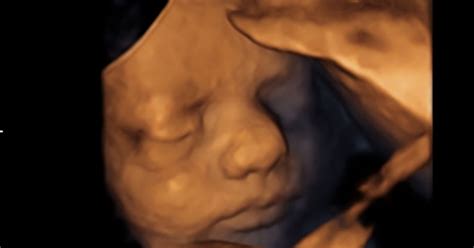

Presenetljivo je, da se razvoj mlečnih zob začne že globoko v nosečnosti. Že v prvih tednih po spočetju se začnejo oblikovati temelji za otrokove zobe. Do konca drugega trimesečja nosečnosti so začetne faze razvoja vseh mlečnih zob že skoraj končane, čeprav zobje tedaj še niso vidni, saj so skriti pod dlesnijo. To pomeni, da se za mlečne zobe svojega otroka nosečnica tako prične skrbeti z zdravim prehranjevanjem in načinom življenja že v času nosečnosti.